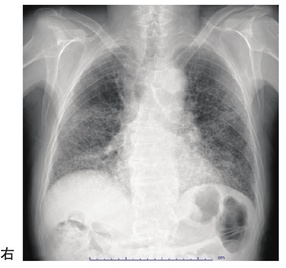

作業療法士実地問題 -

第59回 午前

73歳の女性。胸部単純エックス線写真を別に示す。考えられる疾患または状態はどれか。

1

気胸

2

間質性肺疾患

3

気管切開術後

4

肺葉切除術後

5

慢性閉塞性肺疾患